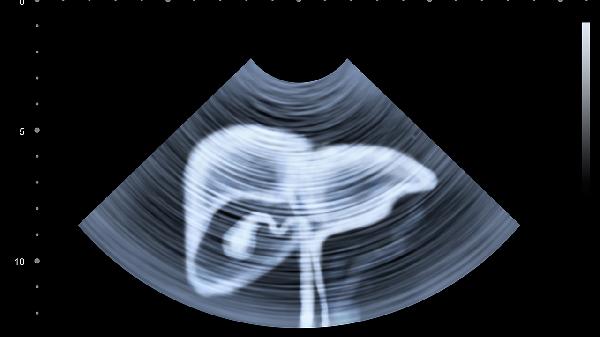

腹部CT能够检查肠道,主要用于评估肠道病变、炎症、肿瘤等问题。CT扫描通过多层面成像技术,可以清晰显示肠道的结构、形态及周围组织情况,帮助医生诊断肠道疾病。

2、肠道梗阻的诊断。腹部CT能够快速识别肠道梗阻的原因,如肠套叠、肠扭转、肿瘤压迫等。通过三维重建技术,CT可以清晰显示梗阻部位及程度,帮助医生制定治疗方案。